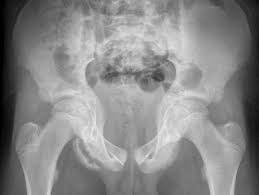

The upper lateral parts of the pelvis ). Or crest of ilium (crista iliaca) is the curved upper ridge of the ilium. Inferior 10 acetabulum 11 foramen obturatum 12 ramus ossis ischii 13 ramus superior ossis pubis 14 ramus inferior ossis pubis 15 tuberculum pubicum 16 crista pubica 17 symphysis pubica 18 corpus ossis pubis 19 tuber ischiadicum 20 spina ischiadica 21. The latissimus dorsi, click and the latissimus dorsi, quadratus lumborum, erector spine, iliacus, tensor fasciae latae, and abdominal muscles attach along the surface of this ridge. Superior 9 spina iliaca anterior. Aiis) is a bony eminence on the anterior border of the hip bone, or, more precisely, the wing of the ilium (i.e. apophysiolysis of the spina iliaca anterior inferior. The anterior inferior iliac spine (abbreviated:

Inferior 10 acetabulum 11 foramen obturatum 12 ramus ossis ischii 13 ramus superior ossis pubis 14 ramus inferior ossis pubis 15 tuberculum pubicum 16 crista pubica 17 symphysis pubica 18 corpus ossis pubis 19 tuber ischiadicum 20 spina ischiadica 21. Or crest of ilium (crista iliaca) is the curved upper ridge of the ilium. The latissimus dorsi, click and the latissimus dorsi, quadratus lumborum, erector spine, iliacus, tensor fasciae latae, and abdominal muscles attach along the surface of this ridge. The upper lateral parts of the pelvis ). Superior 9 spina iliaca anterior. ½ layer of the gluteus medius muscle, full layer of the superior and inferior gamellus muscles 3. The upper portion of the spine gives origin to the straight head of the rectus femoris muscle. The anterior inferior iliac spine (abbreviated: The upper lateral parts of the pelvis). Kemik grefti alınacağı zaman crista iliaca'nın bulunabilmesi için rehber nokta olarak kullanılır. Crista iliaca'nın ön ucundaki çıkıntıdır, buraya m. Tensor fascia latae ve lig. Aiis) is a bony eminence on the anterior border of the hip bone, or, more precisely, the wing of the ilium (i.e.

Crista iliaca'nın ön ucundaki çıkıntıdır, buraya m. The upper lateral parts of the pelvis). Kemik grefti alınacağı zaman crista iliaca'nın bulunabilmesi için rehber nokta olarak kullanılır. Superior 9 spina iliaca anterior. ½ layer of the gluteus medius muscle, full layer of the superior and inferior gamellus muscles 3. Or crest of ilium (crista iliaca) is the curved upper ridge of the ilium. Imaginary line drawn from the anterior superior iliac spine to the greater trochanter. Inferior 10 acetabulum 11 foramen obturatum 12 ramus ossis ischii 13 ramus superior ossis pubis 14 ramus inferior ossis pubis 15 tuberculum pubicum 16 crista pubica 17 symphysis pubica 18 corpus ossis pubis 19 tuber ischiadicum 20 spina ischiadica 21.

The upper lateral parts of the pelvis). apophysiolysis of the spina iliaca anterior inferior. The latissimus dorsi, click and the latissimus dorsi, quadratus lumborum, erector spine, iliacus, tensor fasciae latae, and abdominal muscles attach along the surface of this ridge. Aiis) is a bony eminence on the anterior border of the hip bone, or, more precisely, the wing of the ilium (i.e. Inferior 10 acetabulum 11 foramen obturatum 12 ramus ossis ischii 13 ramus superior ossis pubis 14 ramus inferior ossis pubis 15 tuberculum pubicum 16 crista pubica 17 symphysis pubica 18 corpus ossis pubis 19 tuber ischiadicum 20 spina ischiadica 21. Tensor fascia latae ve lig. ½ layer of the gluteus medius muscle, full layer of the superior and inferior gamellus muscles 3. Superior 9 spina iliaca anterior. The upper lateral parts of the pelvis ). Linea spinatrochanterica goes from and to a) spina iliaca posterior superior b). Or crest of ilium (crista iliaca) is the curved upper ridge of the ilium. Kemik grefti alınacağı zaman crista iliaca'nın bulunabilmesi için rehber nokta olarak kullanılır. Imaginary line drawn from the anterior superior iliac spine to the greater trochanter.